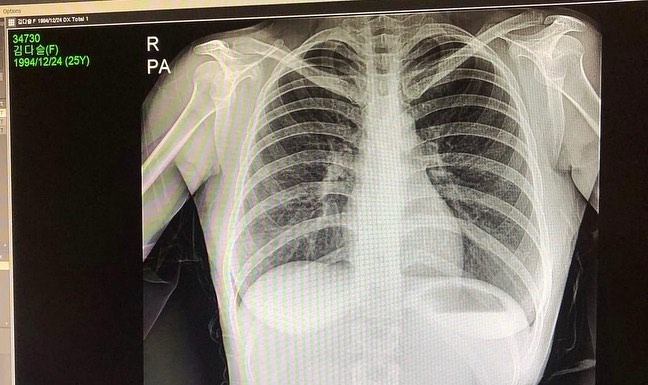

不過,擁有如此姣好的身材,其實也讓 Zzyuri 遭受到不少質疑,先前就有網友酸她是靠「抽肋骨、隆乳」才有現在的凹凸曲線,由於類似的謠言越傳越誇張,讓她不得不出面澄清。去年,她在 IG 貼出一組 X 光照,從照片中可以看出,她的肋骨數量正常,胸部也不存在假體,正面打臉了所有質疑她的網友。

而 Zzyuri 也表示從兩年前開始,就陸續有網友質疑她去隆乳,現在又說她跑去抽肋骨,為了自證清白,她再次強調自己從未動過整形手術,並首次公開 X 光照,希望能遏止謠言散佈。貼文一曝光,粉絲們也都表示力挺,還有人留言喊話:「不要去做隆胸手術,自然就是美」,而 Zzyuri 看到後也回了一句:「是的」表示認同。